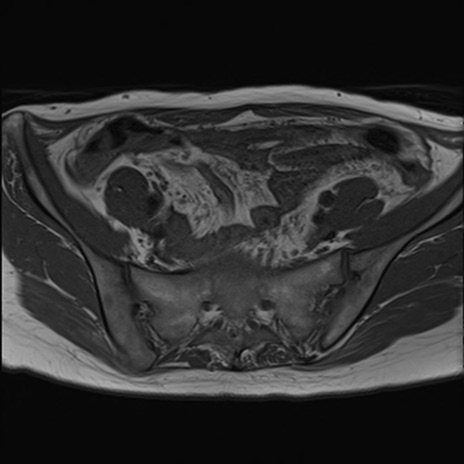

症例39 T1WI(横断像)

MRI(4日後)